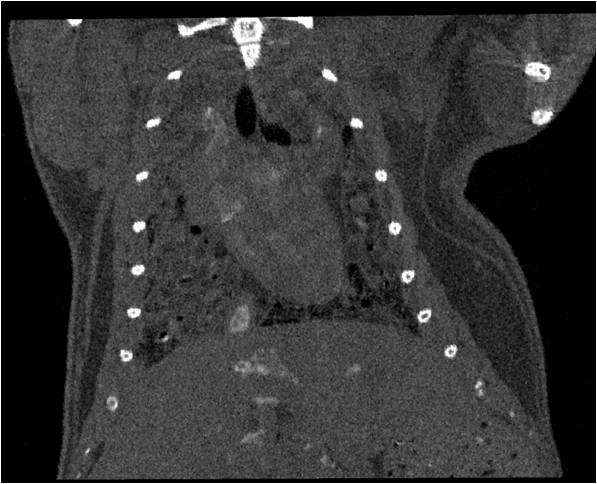

腫瘤血管生成

肺纖維3.jpg

肺轉移

小鼠模式,22.5μm像素

正常

正常.jpg

8天                                                                  14天

8天.jpg  14天.jpg

無(wú)造影劑注入                                     造影劑注入